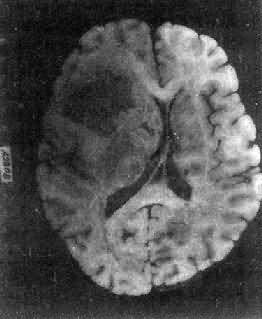

图16-23 星形胶质细胞瘤 左大脑半球肿胀,肿瘤边界不清,部分呈胶冻状 镜下,肿瘤细胞形态多样,可相似于纤维型星形胶质细胞、原浆型星形胶质细胞和肥胖星形胶质细胞,故分别称为纤维型、原浆型和肥胖型星形胶质细胞瘤。前二者为良性肿瘤,后者性质介于良恶性之间。如肿瘤细胞出现间变,细胞密度增大,异型性明显,核深染,出现核分裂像,毛细血管内皮细胞增生,则为间变性星形胶质细胞瘤,为恶性肿瘤。 高度恶性的星形胶质细胞瘤称为多形性胶质母细胞瘤(glioblastoma multiforme),多见于成人。肿瘤好发于额叶、颞叶白质,浸润范围广,常可穿过胼胝体到对侧,呈蝴蝶状生长(图16-24)。瘤体因常有出血坏死而呈红褐色。镜下,细胞密集,异型性明显,可见怪异的单核或多核瘤巨细胞。出血坏死明显,是其区别于间变性星形胶质细胞瘤的特征。毛细血管明显增生,内皮细胞增生、肿大,可导致管腔闭塞和血栓形成。肿瘤发展迅速,预后极差,患者多在2年内死亡。

图16-24 多形性胶质母细胞瘤 发生于儿童、青少年的毛发细胞型星形胶质细胞瘤,生长极为缓慢。有报道称患者在不完全切除肿瘤后有带瘤存活达40年者。该瘤常位于小脑、第四脑室底部、第三脑室、丘脑和视神经。其形态特点是由双极性的肿瘤细胞两端发出纤细的毛发状突起。即使有毛细血管增生,本瘤的预后仍相对较好。 应该指出,同一肿瘤的不同区域,瘤细胞可有不同的形态特征,且分化程度也不尽相同,因此肿瘤的分型仅具有相对的意义。 星形胶质细胞瘤的细胞骨架含有胶质纤维酸性蛋白(GFAP),免疫组织化学染色呈阳性反应,是该肿瘤的特异标志。 2.少突胶质细胞瘤(oligodendroglioma) 约占颅内胶质瘤的5%,主要见于30~40岁的成人,男女发病的机会相等。本瘤绝大部分位于大脑半球皮质的浅层,尤以左额叶为多见。 肉眼观,肿瘤呈灰红色边界清楚的球形肿块,位于白质和邻近的皮质,并可累及软脑膜。囊性变、出血和钙化颇为常见,其中钙化灶对X线诊断有一定帮助。 镜下,瘤细胞大小均匀,形态单一,弥漫排列,胞核居中着色深,胞浆空,环绕胞核形成空晕。间质富有血管,有不同程度的内皮细胞增生。约有20%病例可出现瘤细胞钙化,其范围大小不一,其中7%为镜下钙化,有时钙化灶较大,可在X线片上显示出来。如肿瘤组织中混有星形胶质细胞瘤成分达到50%,则称混合性少突星形胶质细胞瘤。 本瘤生长缓慢,病程可长达10~30年,临床表现多为癫痫和局部性瘫痪。少数生长迅速,酷似多形性胶质母细胞瘤,预后不佳。 3.室管膜(细胞)瘤(ependymoma)起源于室管膜细胞,患者多为儿童和青少年。本瘤占颅内胶质瘤的5%~6%,多见于第四脑室,其次为侧脑室、第三脑室和导水管。脊髓病变多发生于腰胝及马尾部。 肉眼观,颅内室管膜瘤呈膨胀性生长,边界清楚,呈球形、分叶状或乳头状,肿瘤多在脑室内生长。切面灰白色,呈均匀或颗粒状,可发生灶性出血甚至坏死或囊性变,有时也可发现点状钙化。 镜下,瘤细胞大小形态一致,呈梭形或胡萝卜形,胞核圆或椭圆,染色质呈细颗粒状,核膜清楚,有核仁。瘤细胞胞浆丰富,突起明显。瘤细胞的排列有二种特征,一是环绕空腔排列成腺管状,形态上与室管膜腔相似,称为菊形团形成,另一是环绕血管形成假菊形团结构,瘤细胞有细长的胞浆突起与血管壁相连(图16-25)。细胞中有神经胶质纤维,以PTAH染色在个别细胞的腔面或胞核旁可见纤毛体,后者与纤毛运动有关,是室管膜细胞的特征性结构。此外,有时还可形成乳头状结构。发生在脊髓圆锥和终丝的肿瘤,乳头状结构轴心中的结缔组织往往富含粘液。